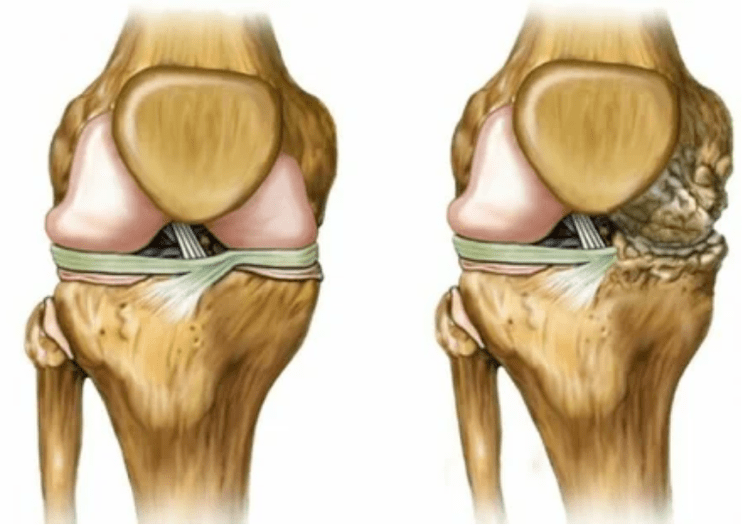

Haiguse viimane aste viib:

- luude patoloogilises protsessis osalemine kõhrepindade all ja kohal;

- Liigese kesta ärritus, piirav liikuvus, mis põhjustab puude 2 kraadi;

- suurenenud kapsli tihedus;

- Vähendades liigese lõhet, mis muutub pildil märgatavaks. Rikkumise etapi määrab diagnostiline-tantgenoloog. Patsient tunneb keerukust või suutmatust jäseme täielikult sirgendada ja painutada;

- liigese deformatsioon, kõhre omandab ebaregulaarse kuju, provotseerides kumerust;

- Patsiendi seisundi halvenemine koos liigese täieliku hävitamisega.